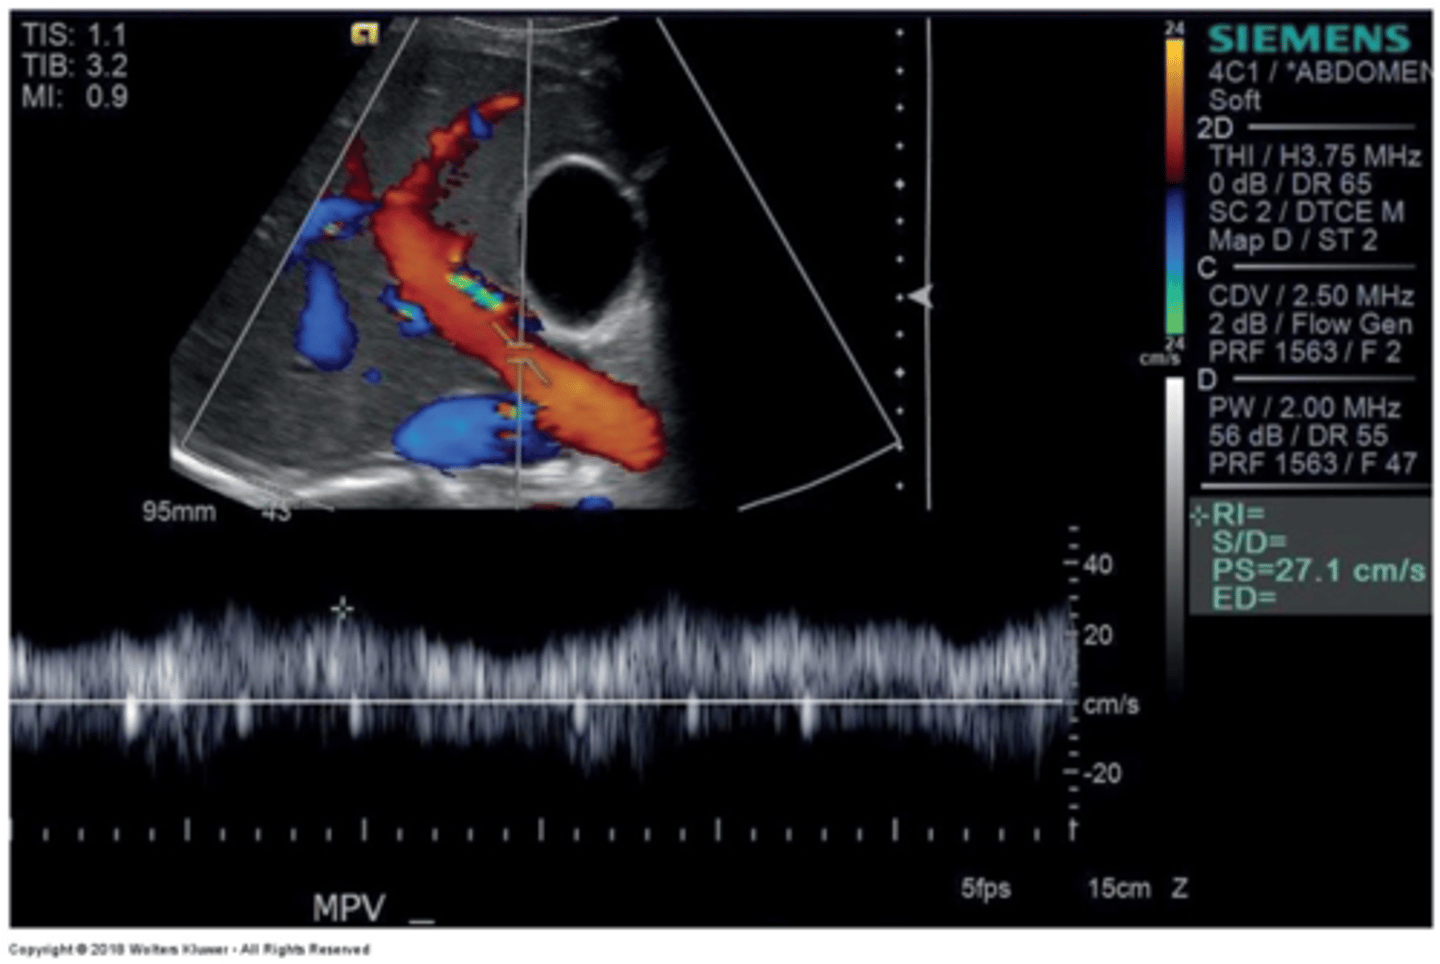

Main Portal Vein Doppler Waveform

Monophasic continuous waveform

Hepatopetal flow (antegrade flow)